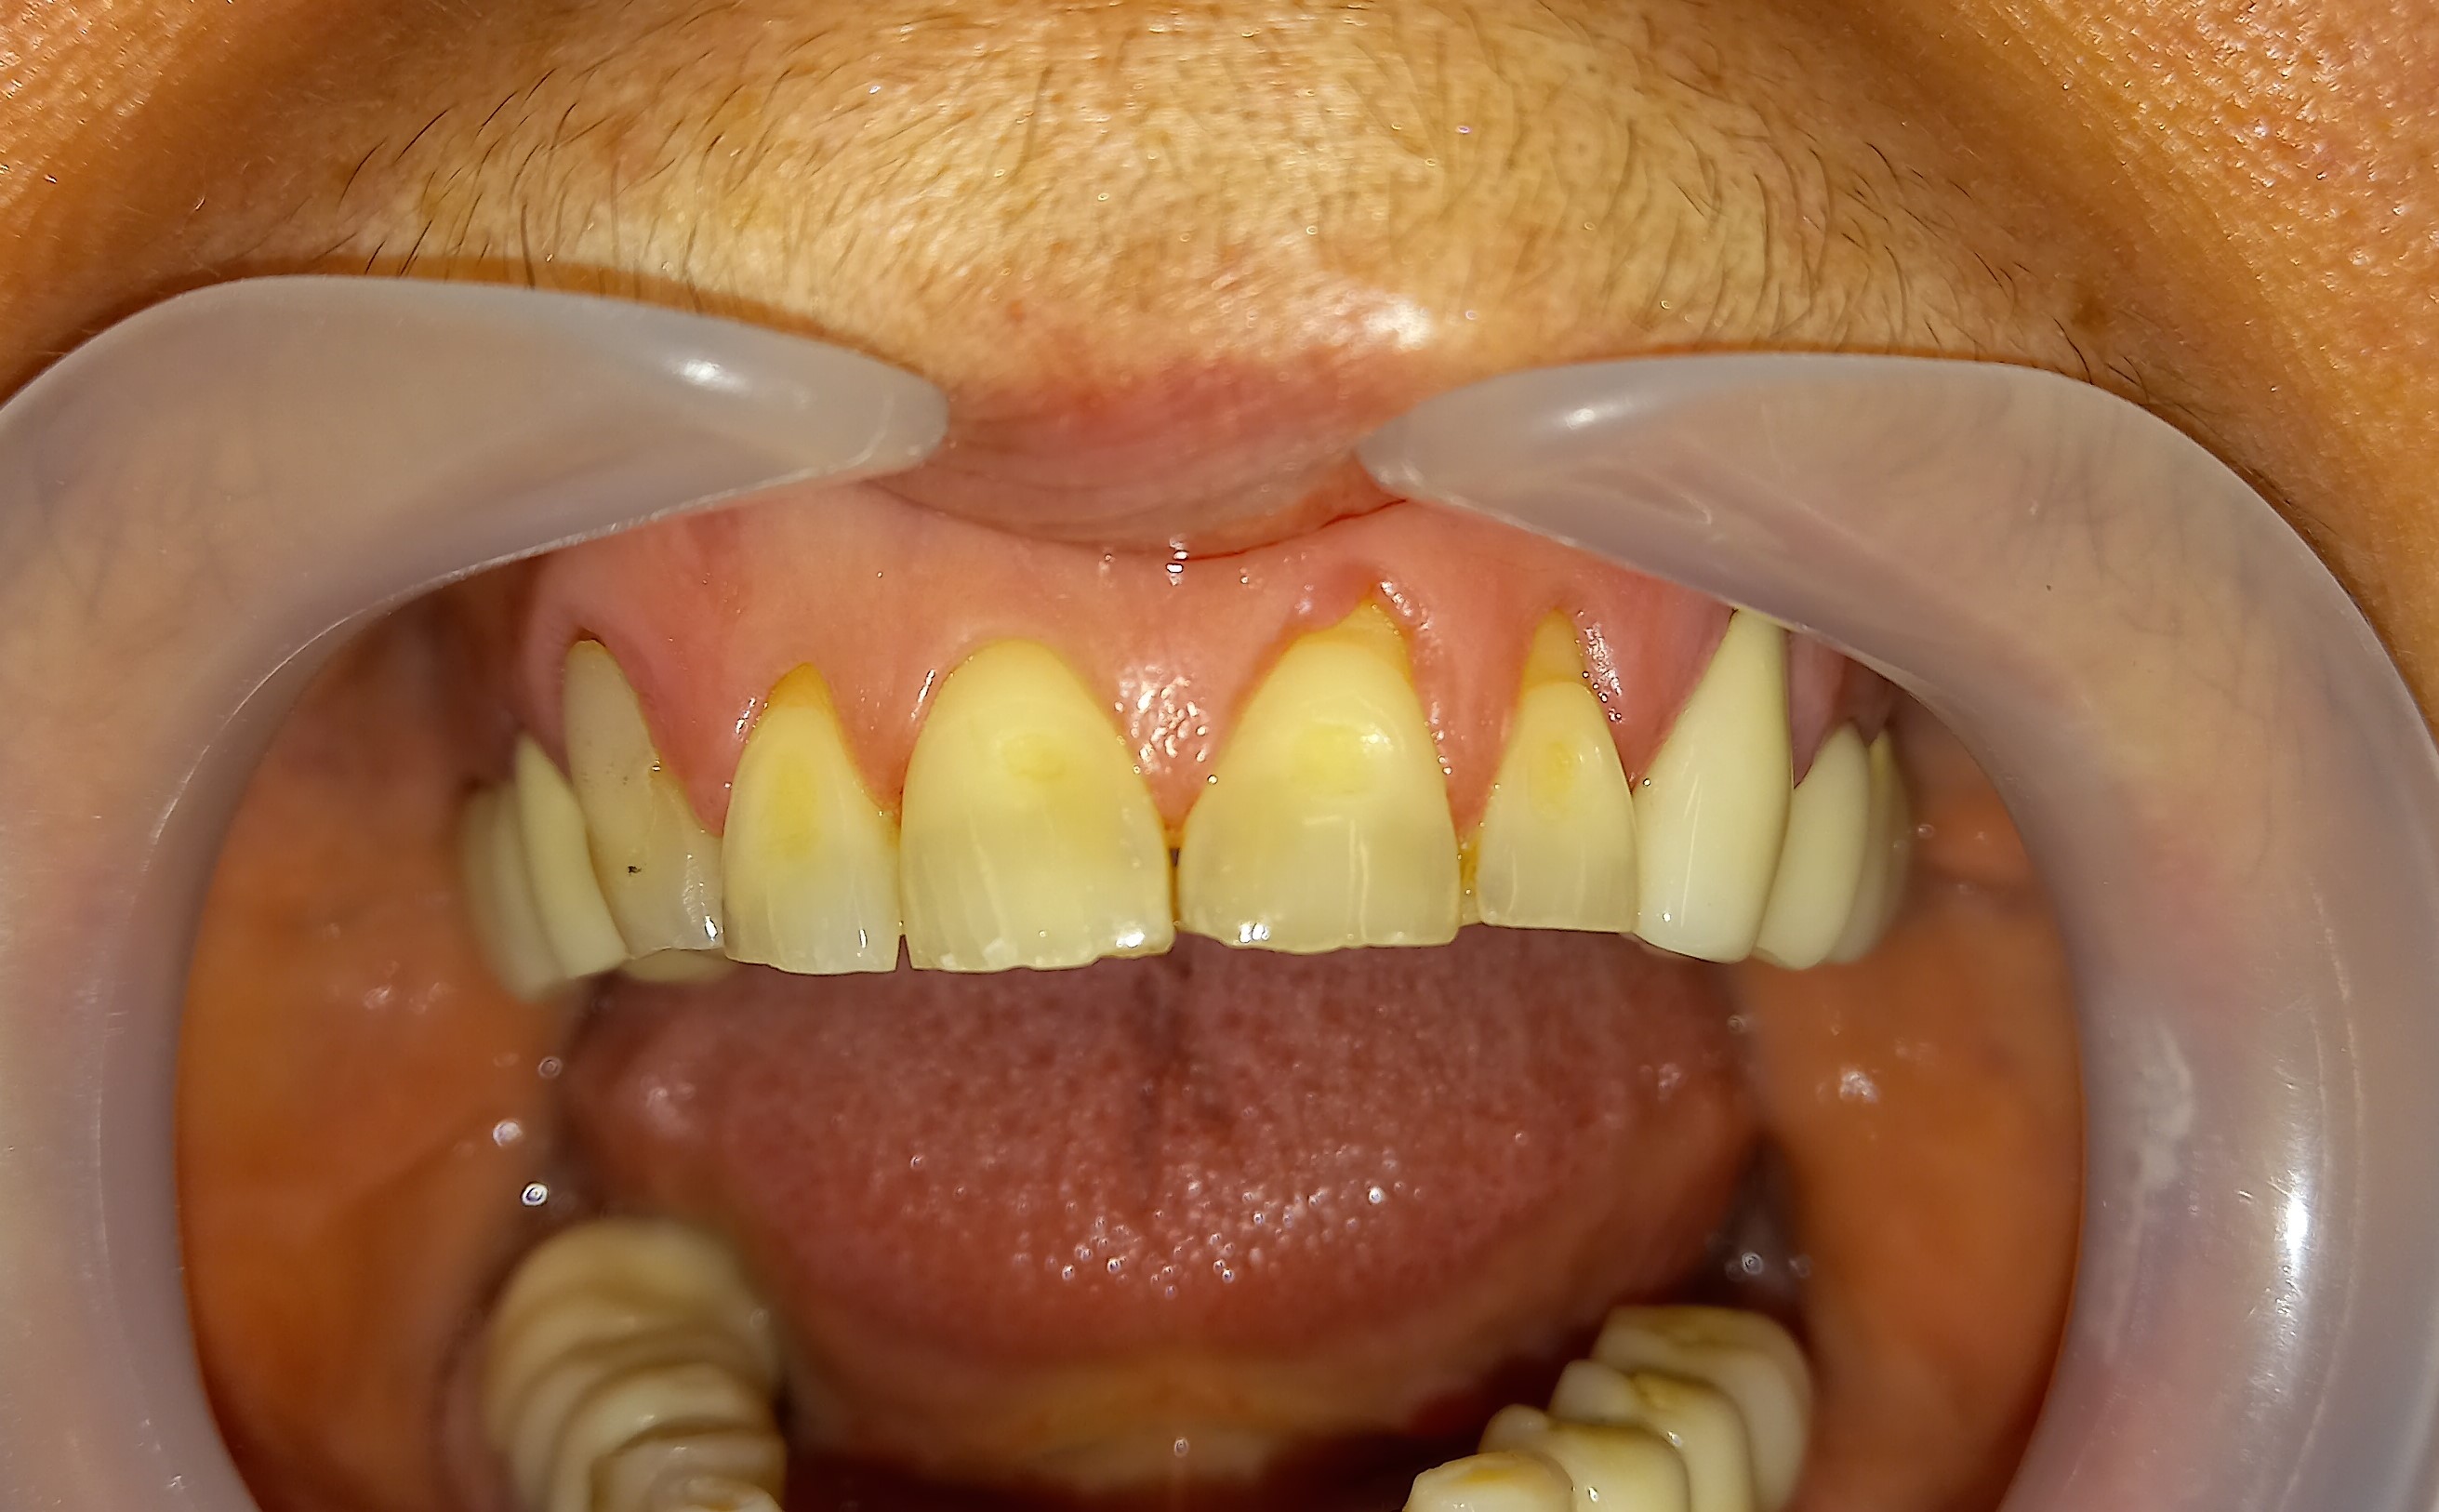

Επανάληψη απονεύρωσης σε τρία άνω πρόσθια δόντια